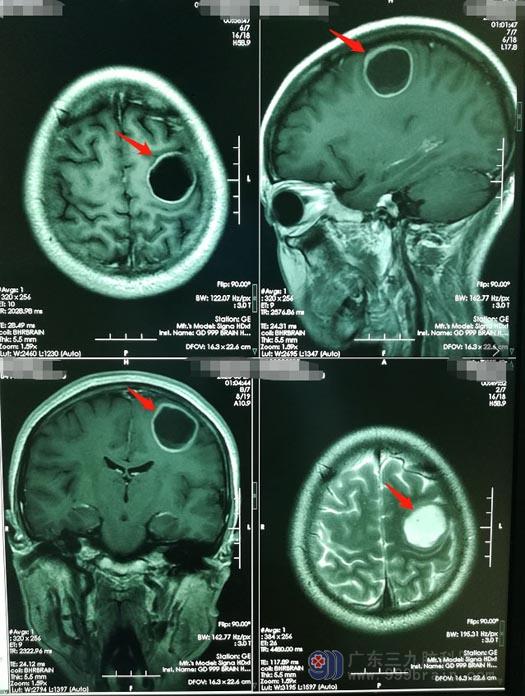

阿兰40岁的时候,平静的生活再次被打破,她的颅内发现了占位病变。最初的症状是右胳膊无力、右手无法独自拿筷子吃饭。已经经历过一场大病的阿兰对自己的身体状况更为敏感,在当地医院进行检查。这一次,检查结果并不好,胸部CT提示:右侧肺尖结节较前增大,双肺新增多发结节,考虑转移瘤,头颅MR:右侧额顶叶占位性病变,考虑转移瘤。

在热心人的帮助下,他们找到了广东三九脑科医院神经外五科。医院副院长、神经外五科主任鲁明带领团队热情地接待了他们。认真分析阿兰的病情后,主管医生告诉阿兰丈夫,患者的症状属于鼻咽癌脑转移后产生的压迫症状,幸运的是,影像学报告提示病灶就只有这一处,通过手术切除肿瘤,可以使压迫症状不再继续加重,提高患者的生活质量,并且能够获得更长的生存期。

在阿兰夫妻及医护团队的密切配合下,神经外五科医生团队为患者实施了“唤醒麻醉下左侧额叶占位切除术”,手术完成顺利。术后第三天,阿兰神志清楚,对答正确,能够遵嘱活动,右手抓握能力改善,未出现任何不良症状。术后磁共振提示:肿瘤全切。

▲手术前